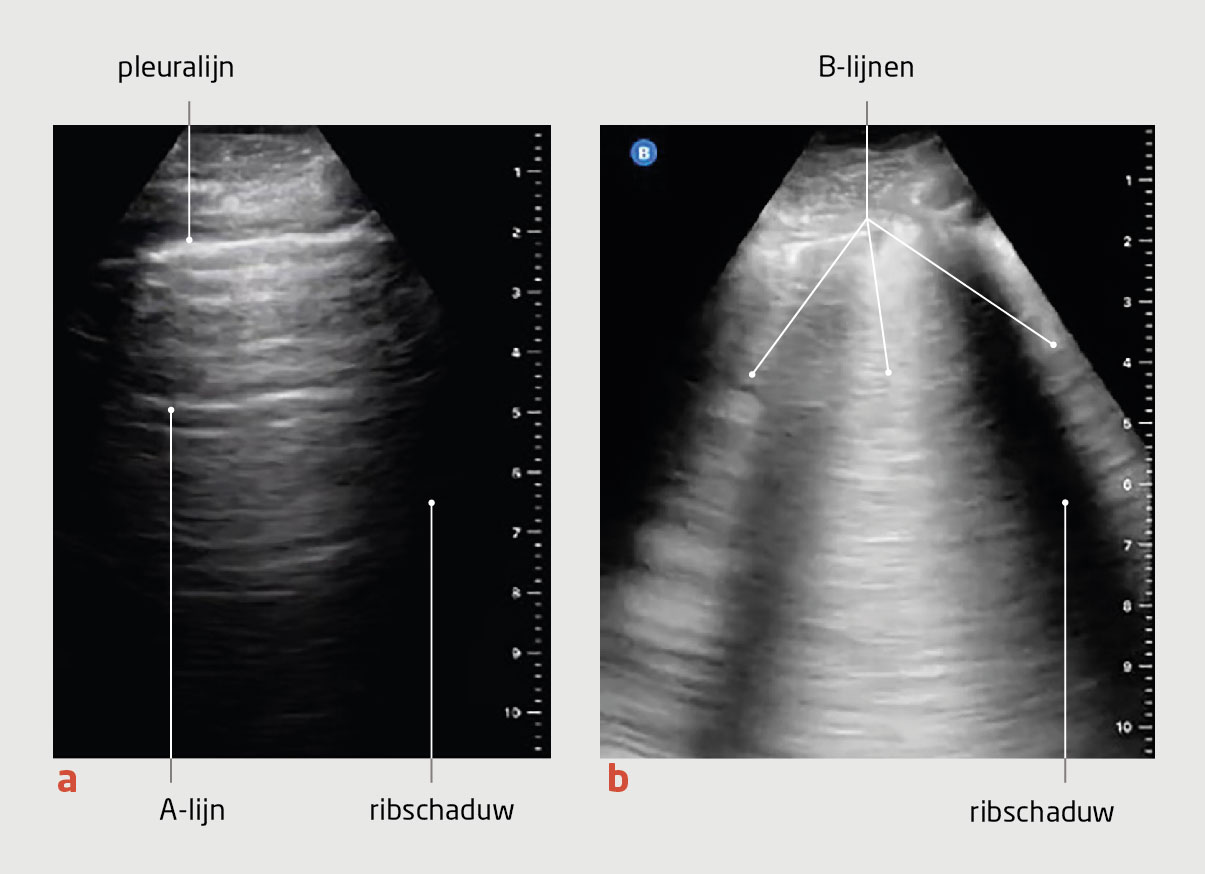

• Het combineren van conventionele methoden met eenvoudig toepasbare point-of-care-echografie (POCUS) helpt om de vullingsstatus nauwkeuriger vast te stellen. Bij dit POCUS-onderzoek beoordeelt men het punt van collaps van de v. jugularis interna, de diameter van de proximale v. cava inferior en de aanwezigheid van pulmonale B-lijnen.